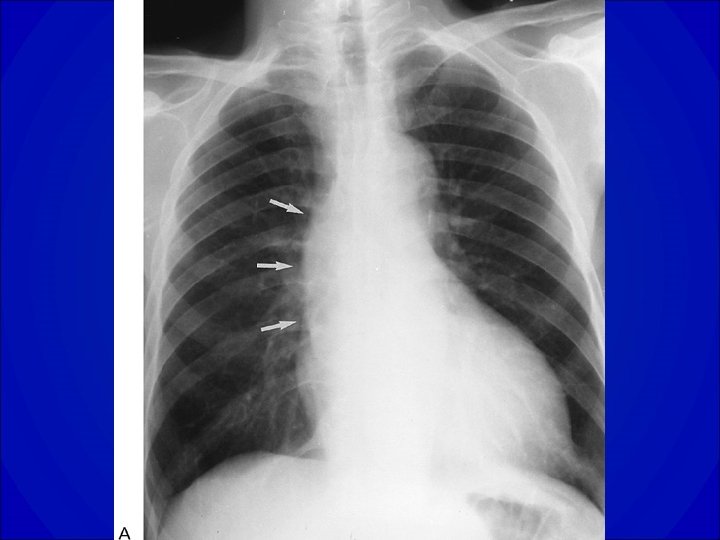

CARDIOMEGALIE Index cardio-thoracique > 0. 6

Diagnostic • ECG Hypertrophie VG • Radiographie de thorax= dilatation du VG • Echocardiographie Trans thoracique ++ -Confirmation et quantification de la fuite -Évaluation du retentissement VG -Lésions associées ? Anévrysme de l’aorte ascendante ? • Scanner et /ou IRM étude de l’aorte initiale si difficultés échographiques

Diagnostic • ECG ACFA, Surcharge auriculaire gauche, Signes d’atteintes VG (HVG, Ondes Q…. ) • Radiographie de thorax= dilatation du VG • ETT +/- ETO -Confirmation et quantification de la fuite -Faisabilité d’une réparation chirurgicale (plastie) -Évaluation du retentissement VG -Lésions associées ?